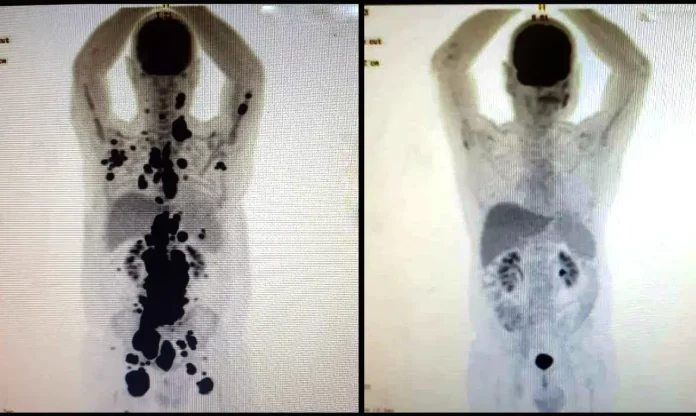

A terapia celular CAR-T Cell tem obtido resultado importante no tratamento de alguns tipos de câncer, por meio da reprogramação das células de defesa do corpo. A tecnologia celular CAR-T é um tipo de imunoterapia que utiliza linfócitos T, células do sistema imunológico responsáveis por combater agentes patogênicos e células infectadas.

O tratamento consiste em retirar e isolar os linfócitos T do paciente, ativá-los, programá-los para conseguirem identificar e combater o câncer e, depois, inseri-los de volta no organismo do indivíduo. Todo o processo pode durar cerca de dois meses. A terapia é feita por meio de infusão intravenosa.

Já o tratamento com as células CAR-T é uma modalidade da imunoterapia, mas que utiliza células de defesa que passaram por modificação genética e foram reprogramadas em laboratório para atingir os tumores.